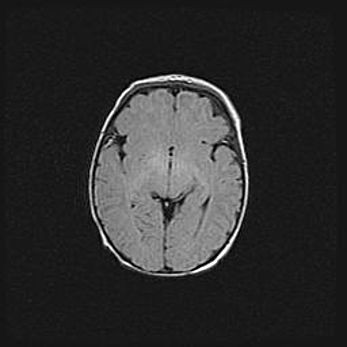

Сообщающаяся гидроцефалия. Кистозная энцефаломаляция головного мозга.

Возраст: 3 месяца 4 дня

Вес: 3100 г

Пол: женский

Окружность головы: 34 см

Срок гестации: 31 неделя

Кистозная энцефаломаляция головного мозга - одна из форм поражения головного мозга в детском возрасте. Характеризуется возникновением множественных и распространённых кист в коре, белом веществе и подкорковых образованиях головного мозга у плодов, новорождённых и детей раннего возраста. Развитие кистозной энцефаломаляции связано с внутриутробной асфиксией и гипотонией, родовой травмой, тромбозом синусов, пороками развития сосудов, инфекциями, сепсисом и другими причинами. Наиболее значимые инфекционные агенты: вирусы простого герпеса, цитомегалии, краснухи, токсоплазмы, энтеробактерии, золотистый стафилококк и другие.